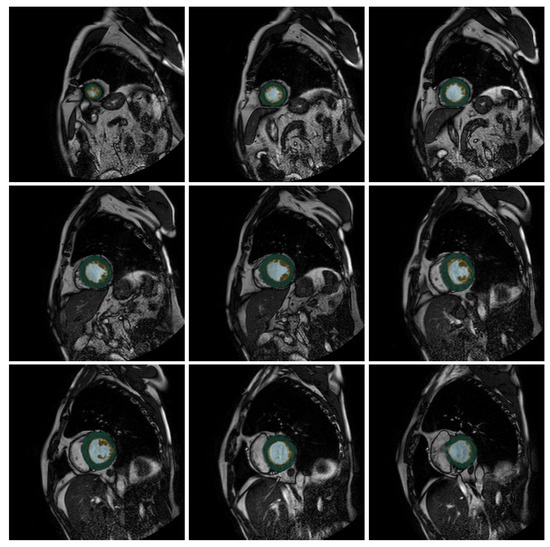

The output of our neural net looks like Figure 1, where we color three different zones: External Layer (EL), Internal Cavity (IC), and Trabecular Zone (TZ) in three different colors. Our U-Net-based proposal takes this output and calculates the VT%, giving us the access to determine if the patient has LVNC.

Figure 1.

Output slices for the patient P241 (from the test set) from the U-Net++. Green indicates the compacted external layer of the left ventricle, yellow the trabecular zone, and light blue the internal cavity.